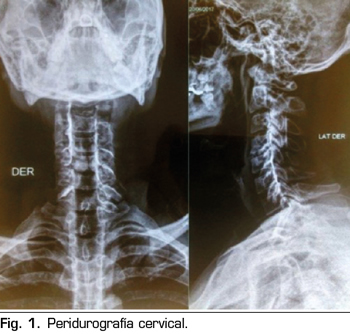

Pasa a recuperación donde hubo regresión completa del bloqueo cervical; el paciente se mantiene estable y con evolución favorable; fue evaluado por el servicio de terapia del dolor, donde se decide observar la permeabilidad del catéter, utilizando una sustancia de contraste iodado no iónico 3 cc, evidenciando en la imagen de “Peridurografía cervical” la difusión del contraste a ambos lados del espacio epidural (Figura 1), procediendo a continuar la analgesia en el postoperatorio a través del catéter epidural cervical con morfina 5 mg, bupivacaína 0,05 % y cloruro de sodio a 0,9 % 90 cc a través de bomba elastómerica a un flujo de 0,5 cc/hora durante 5 días. Se realizó el seguimiento durante la hospitalización, con controles en el postoperatorio inmediato y al primer día, teniendo un EVA 0/10, en estas dos evaluaciones, sin presentar ninguna complicación; fue dado de alta el 2.º día del postoperatorio con la infusión por bomba elastómerica, con un EVA 0/10, reevaluándose al 5.º día del postoperatorio por consultorio externo de terapia del dolor, presentando un EVA 0/10 y sin complicaciones desde el alta (Figura 2), procediendo al retiro del catéter epidural.